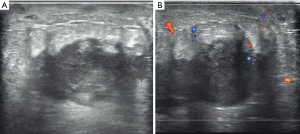

In our study, the maximum size of breast lesions in 6 cases ranged from 1.2 to 4.5 cm, and 1 case with a diffused breast lesion was identified (Figure 1). The shape of breast metastases in 5 (5/7, 71.4%) cases was irregular, with the other 2 (2/7, 28.6%) cases having an oval shape (Figure 2). The margin of metastases in 6 (6/7, 85.7%) cases was indistinct, while in the remaining case the margin was noted to be well circumscribed. The lesions were hypoechoic in all cases (7/7, 100.0%) and had heterogeneous internal echogenicity in 5 (5/7, 71.4%) cases, while homogeneous internal echogenicity was found in 2 (28.6%) cases. The lesion orientation of 6 (6/7, 85.7%) cases was parallel (wider than tall), 3 (3/7, 42.9%) cases showed enhancement posterior feature (Figure 3), and 1 (1/7, 14.3%) case had a feature of posterior acoustic shadowing. Microcalcification was not observed in any patient. Color Doppler US detected blood flow in 2 (2/7, 28.6%) cases. Associated secondary signs, including edema and skin thickening, were found in 5 (5/7, 71.4%) cases. The final BI-RADS assessment categories were BI-RADS 3 in 1 (1/7, 14.3%) case, BI-RADS 4A in 1 (1/7, 14.3%) case, BI-RADS 4B in 1 (1/7, 14.3%) case, BI-RADS 4C in 3 (3/7, 42.9%) cases, BI-RADS 5 in 1 (1/7, 14.3%) case.

The common US features of primary breast cancer are irregular, not parallel, indistinct, irregular, hypoechoic, homogeneous masses with microcalcification and posterior acoustic shadowing (19). The common US features of breast metastases from lung cancer are nodules that are irregular, indistinct, hypoechoic, and parallel masses without calcification. The maximum size of breast metastases from lung adenocarcinoma was larger than that of large cell and small cell lung cancer. In addition, internal echogenicity was homogeneous in patients with large cell and small cell lung cancer, while it was heterogenous in patients with adenocarcinoma. Most lesions were parallel to the skin. Posterior acoustic enhancement was also observed in our study. This is different from the US feature of primary breast cancer, where posterior acoustic shadowing is most typical (20). However, we still observed 1 patient with a diffused breast metastasis featuring posterior acoustic shadowing, which, to our knowledge, is the first report of these features in breast metastases. Calcification, which is rarely observed in metastasis to the breast, may be helpful in distinguishing stage IV disease from a primary breast cancer. Only 1 prior study has reported a case of calcifications in lung cancer metastatic to the breast (13). Color blood flow signal was detected in 2 patients, which is different from the abundant vascularity of primary breast carcinoma (21). Sippo et al. (20) and Moreno-Astudillo et al. (22) reported that the US manifestation of other cancer metastases to the breast were round or oval hypoechoic lesions, which could be diagnosed as benign nodules. This study also observed a case of metastatic small cell lung cancer to the breast, which demonstrated an oval shape and indistinct margin, and homogeneous internal echogenicity. In contrast, Luh et al. (23) reported 2 small lung cancer masses with a distinct margin and heterogeneous internal echogenicity.